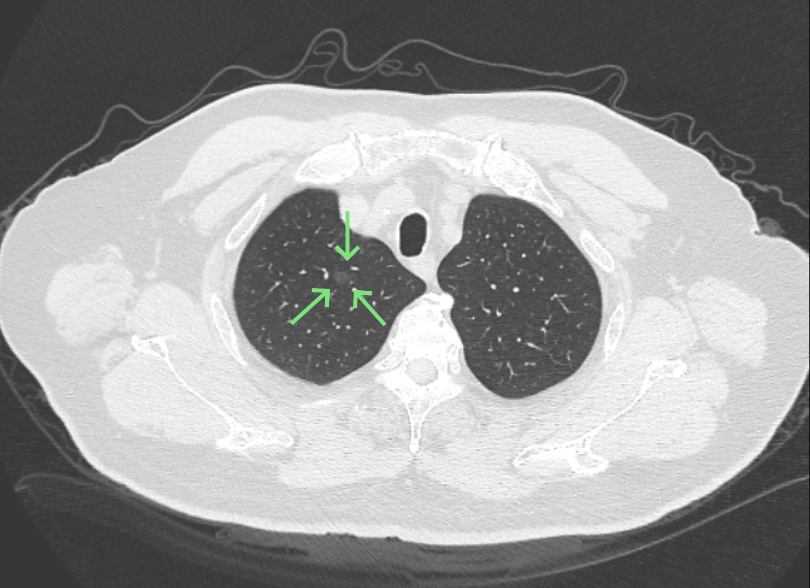

影像展示与分析:

方形的是25年的,红色的主病灶,磨玻璃密度伴少许略偏高点密度,但还说不上典型混合磨玻璃病灶,考虑原位癌或微浸润性腺癌可能性大;蓝色的轮廓与边界欠清,位置靠上叶中央,无法段切或楔切;黄色的多发均淡而纯,分布在两肺。圆形粉色的是主要的两处23年时的样子,对比说不上很明显进展。鉴于若手术得切肺叶,何况两肺他处仍的结节,年纪又74了。我倾向保守点,先6-9个月复查,等进展并风险增加再来考虑怎么办的事。意见供参考!

病灶没有确切纵隔窗可见的实性成分,但与血管关系较为密切。